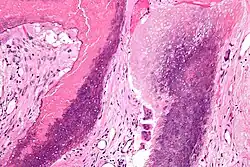

| Histopathology of pilomatricoma, high magnification, H&E stain, showing the characteristic components of basaloid cells and ghost cells. | |

The characteristic components of a pilomatricoma include a stroma of fibrovascular connective tissue surrounding irregularly shaped, lobulated islands containing basaloid cells (being darkly stained, round or elongated, with indistinct cell borders and minimal cytoplasm, with nuclei being round to ovoid, deeply basophilic and generally prominent nucleoli), which abruptly or gradually transitions into ghost cells (having abundant, pale, eosinophilic cytoplasm, well defined cell borders and a central clear area, but only faint traces of nuclear material), which in turn may transition into keratinaceous to amorphous necrosis.[11]

The presence of calcifications with foreign-body giant cells is common within the tumors.[12]